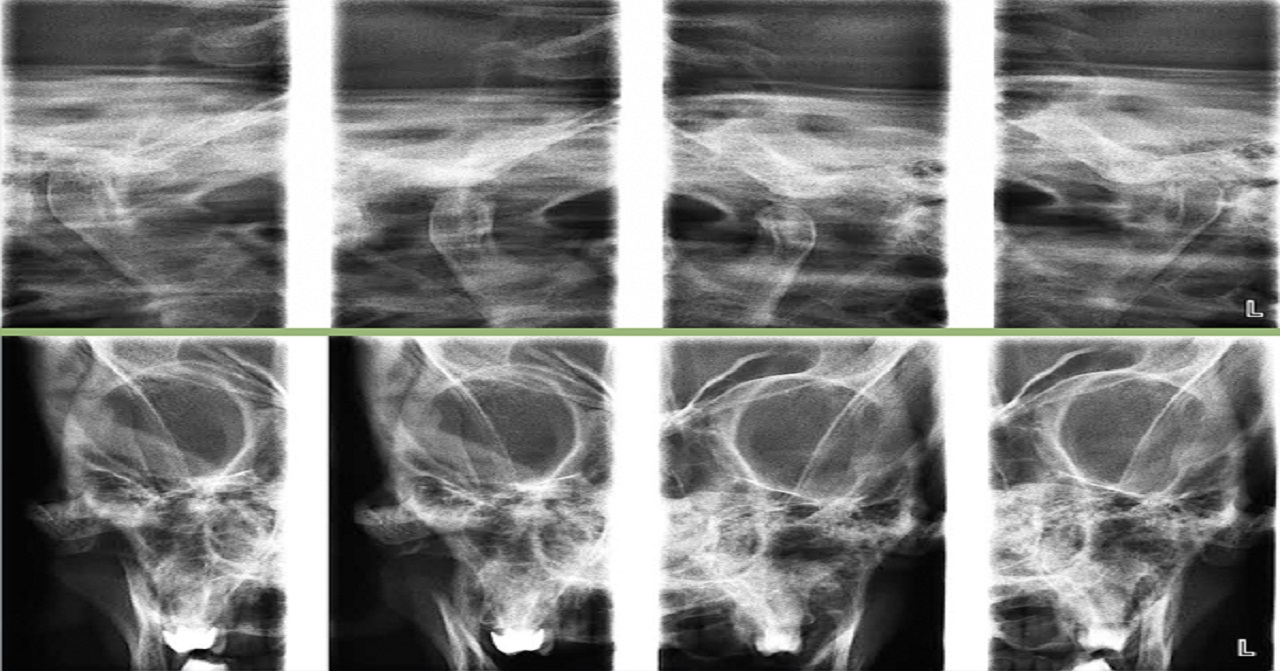

ATM

El estudio radiográfico combinado de ATM está indicado para la valoración de disfunciones temporomandibulares así como fracturas condilares y subcondilares; este estudio comprende de dos radiografías de exposición lateral y posteroanterior de la articulación temporomandibular en posición abierta y cerrada.